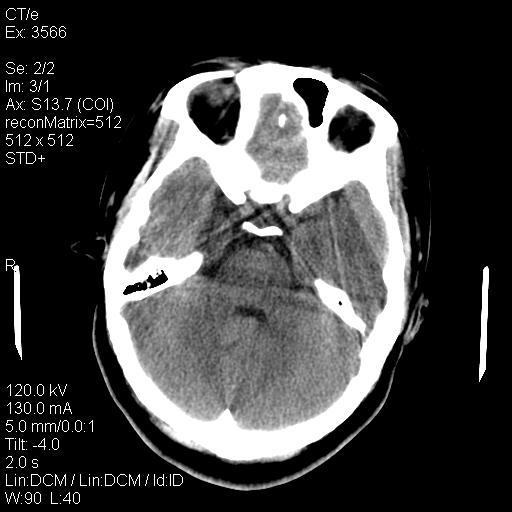

标题: CT9947:女,20岁,妊娠9个月,突然癫痫症状 [打印本页]

标题: CT9947:女,20岁,妊娠9个月,突然癫痫症状

双侧脑白质缺血缺氧性改变,并高度可疑“蛛网膜下腔出血”。

后可复性脑病,

考虑 妊娠子痫或妊高征

双侧脑白质缺血缺氧性改变.

考虑先兆子痫\\子痫致he,建议mri除外有无合并静脉窦血栓形成.

考虑pres

的确应该考虑可逆性后部脑病综合症--pres。感谢天南地北老师的指引,又学了一招儿,开心,呵呵!

考虑可逆性后部脑病综合症